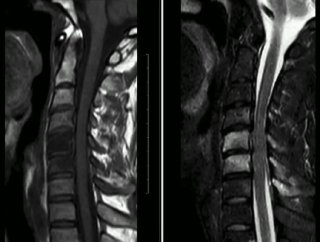

Пациент 35 лет. Жалобы на онемение правой руки. Других жалоб нет.

Характер травмы:

Упал с велосипеда головой вниз.